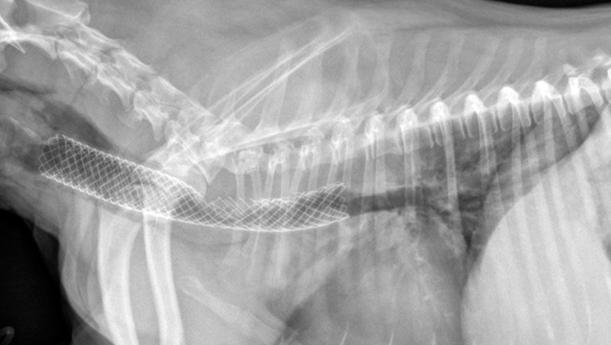

经验丰富的兽医会建议在小狗气管外侧或气管内实施气管支架置入术。这可以防止塌陷。

支架支撑气管打开并阻止气道阻塞。90%的病例显示临床症状迅速改善。

但令人感到不幸的是,小狗可能需要服用以上所列出的药物之一,并且会产生一些并发症,需要重点护理。

气管塌陷的外科治疗的小狗

你可能会问,气管支架置入术的并发症有哪些?

虽说目前的医疗比往日的进步不少。但是,气管支架置入术必须由经验丰富,经过技术培训的兽医才可以进行。

如果在小狗气管内放置了尺寸不适合的支架,则容易产生与支架相关的并发症,如支架发生了位置移动,气管出现骨折情况。

另外,异物在体内同样容易发生感染,进一步发展成炎症。高达40%的放置气管支架的病例可能需要在其生命的某个阶段进行第二次手术。

但经过气管支架置入术后,大多数小狗都能在24小时左右内出院。

气管支架置入术